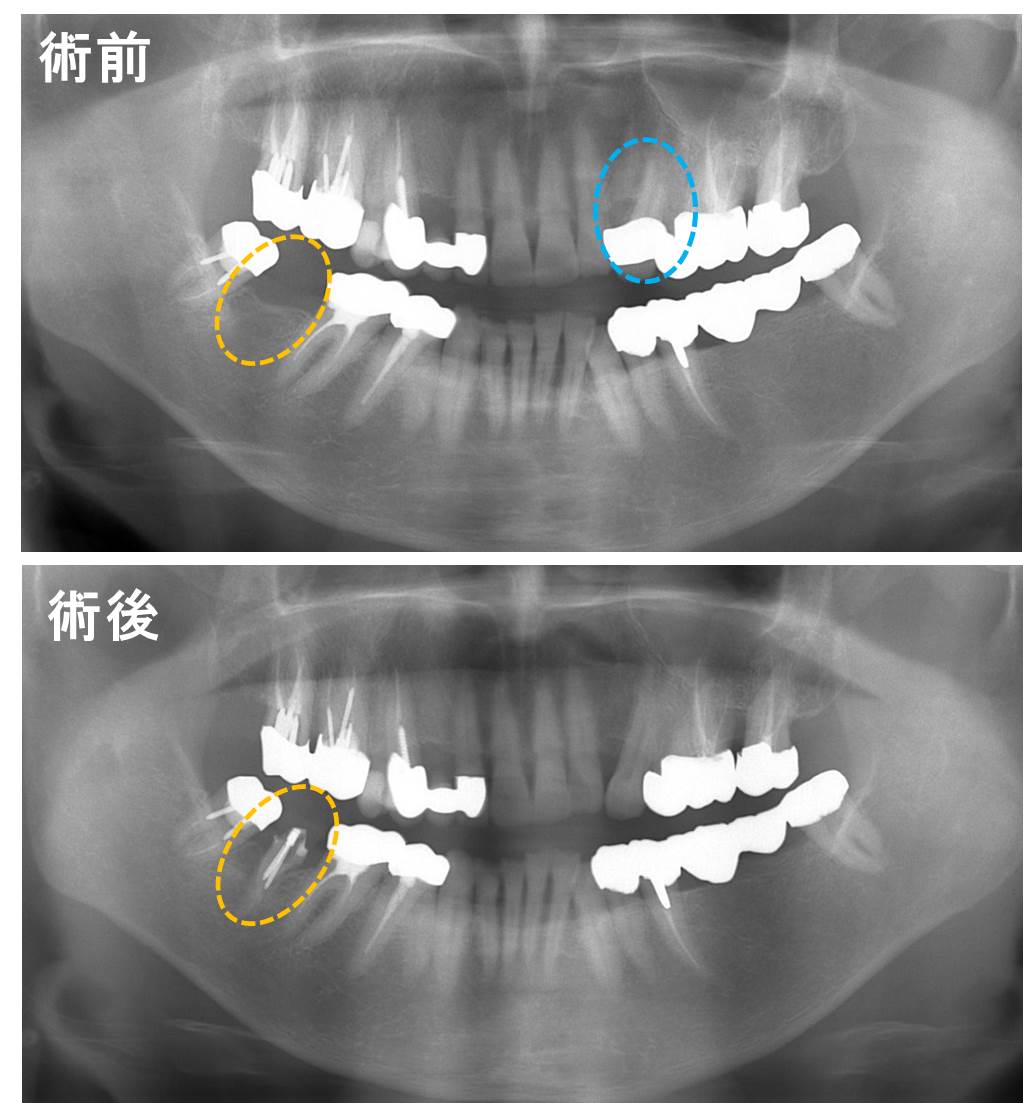

下は術前、術後のレントゲン像です。青○部分の歯をオレンジ○へ移植した状態です。この術後のレントゲンは根管治療終了後で3ヶ月後の写真です。